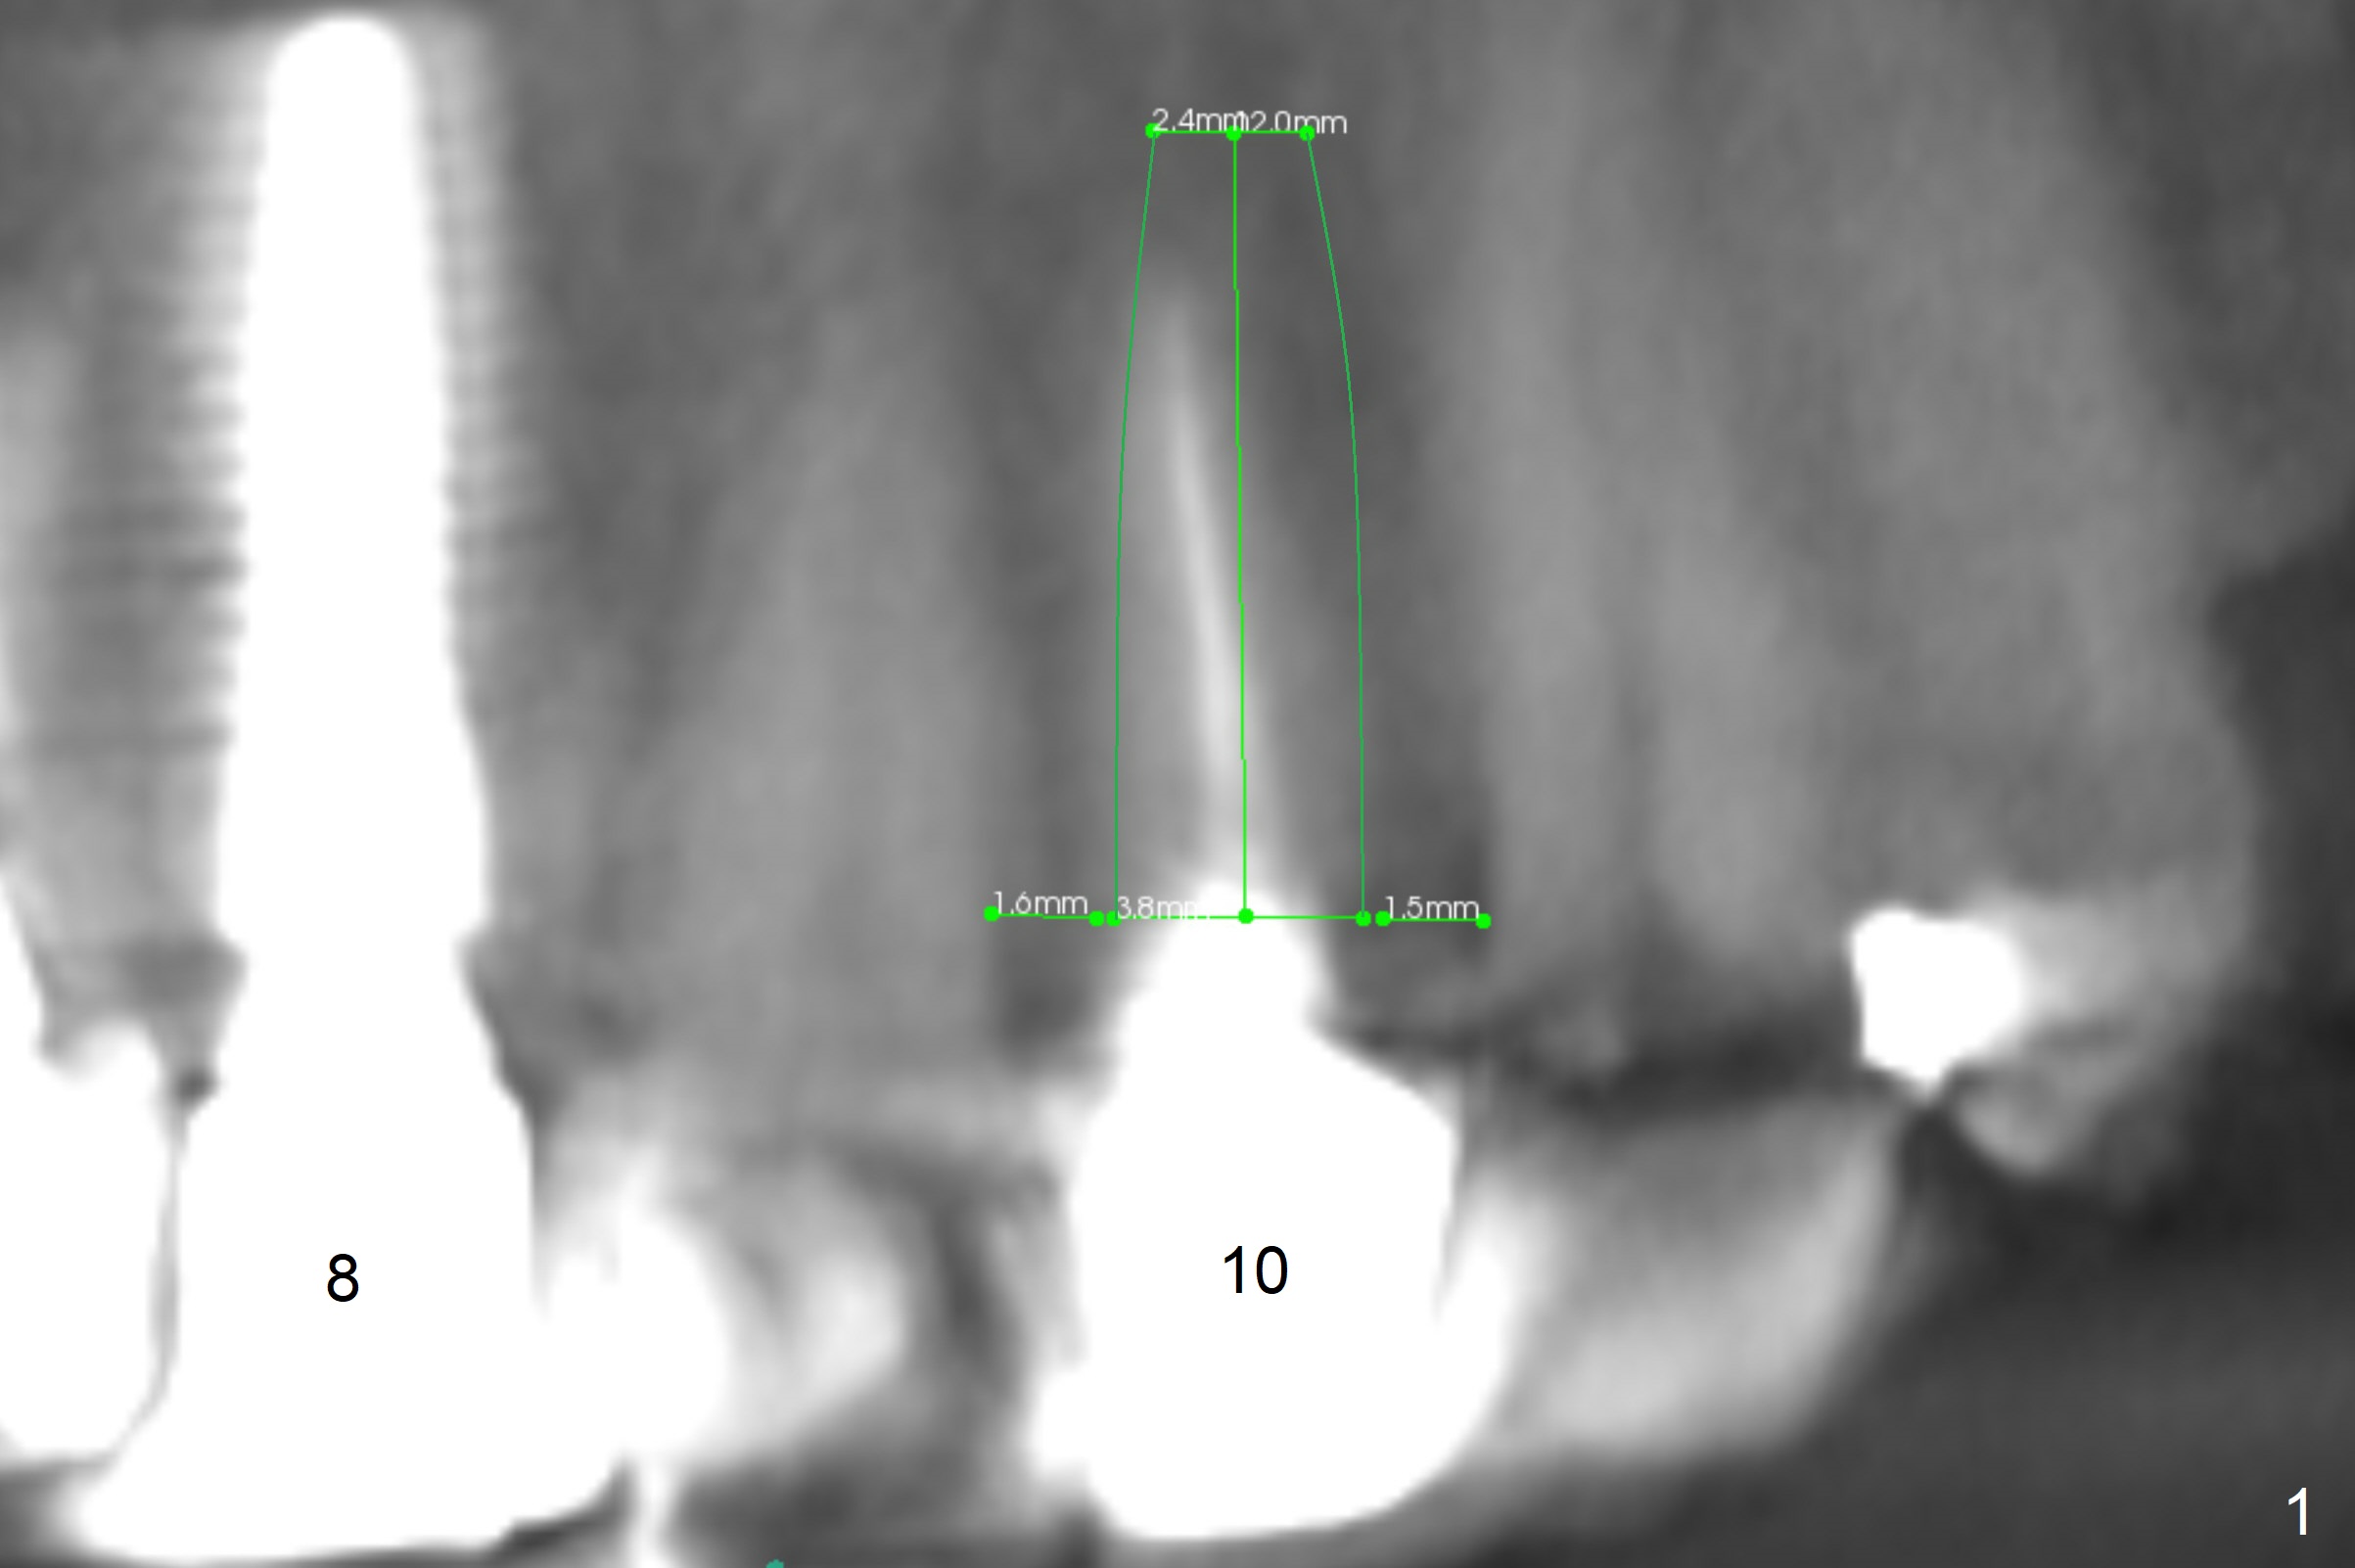

A 37-year-old woman needs an implant at #10 because of crown recementation twice (Fig.1). The smallest 2-piece implant, 3.8 mm, appears to be larger than the root. The implant may perforate the buccal apical concavity (Fig.2 arrowheads). Measure the extracted root. If it is wider than 3.8 mm mesiodistally, place the 2-piece implant. Otherwise use a 3 mm 1-piece one. Do not forget the angled one. Retrospectively, the 3.8 mm implant is large for the site. A 3.0 or 2.5 mm one is more appropriate (Fig.2).